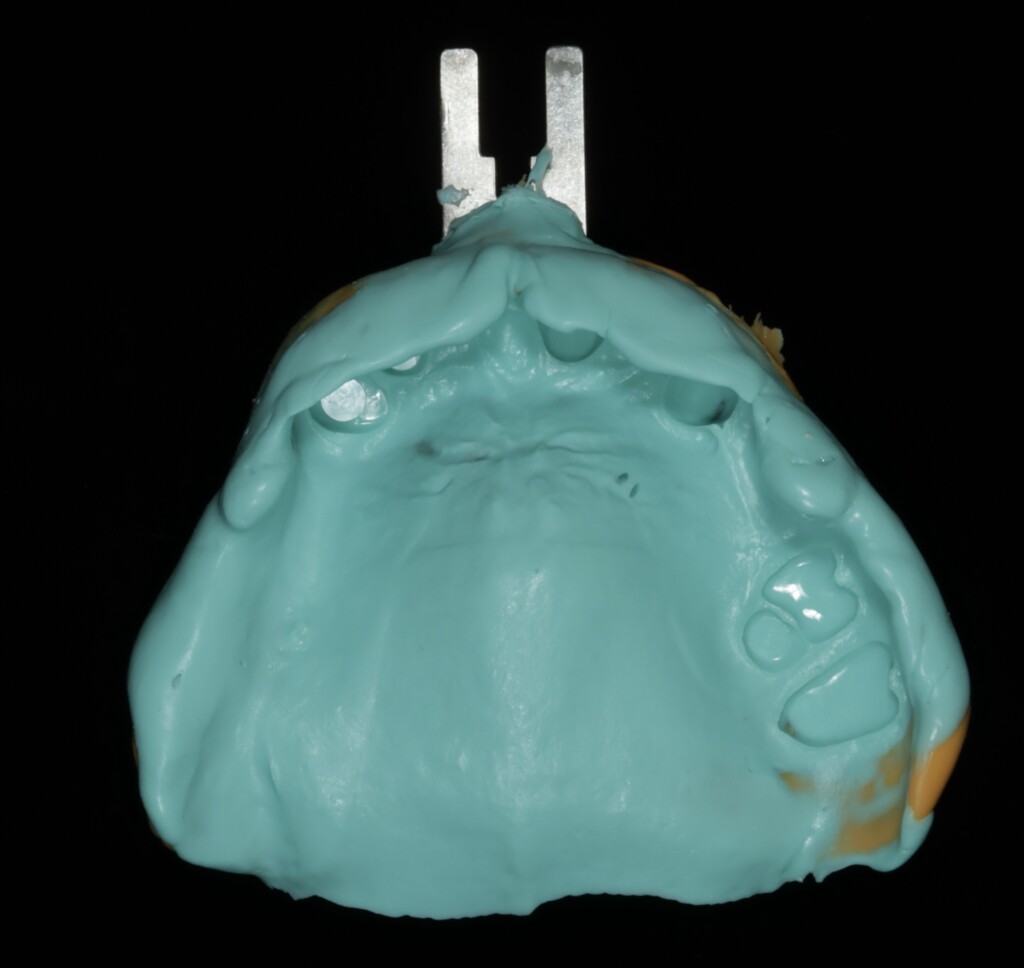

精密な入れ歯を製作するうえでは、この「歯ぐきの沈み込み(粘膜被圧)」を考慮し、実際に噛んだときに近い状態を再現することが重要です。そこで今回は、機能時に近い被圧状態を再現するために「閉口機能印象」を行いました。口を閉じて噛む力が加わった状態で型取りを行うことで、使用時に近い粘膜の状態を反映でき、結果として外れにくく安定した入れ歯の製作につながります。

閉口機能印象(上顎)

閉口機能印象(下顎)